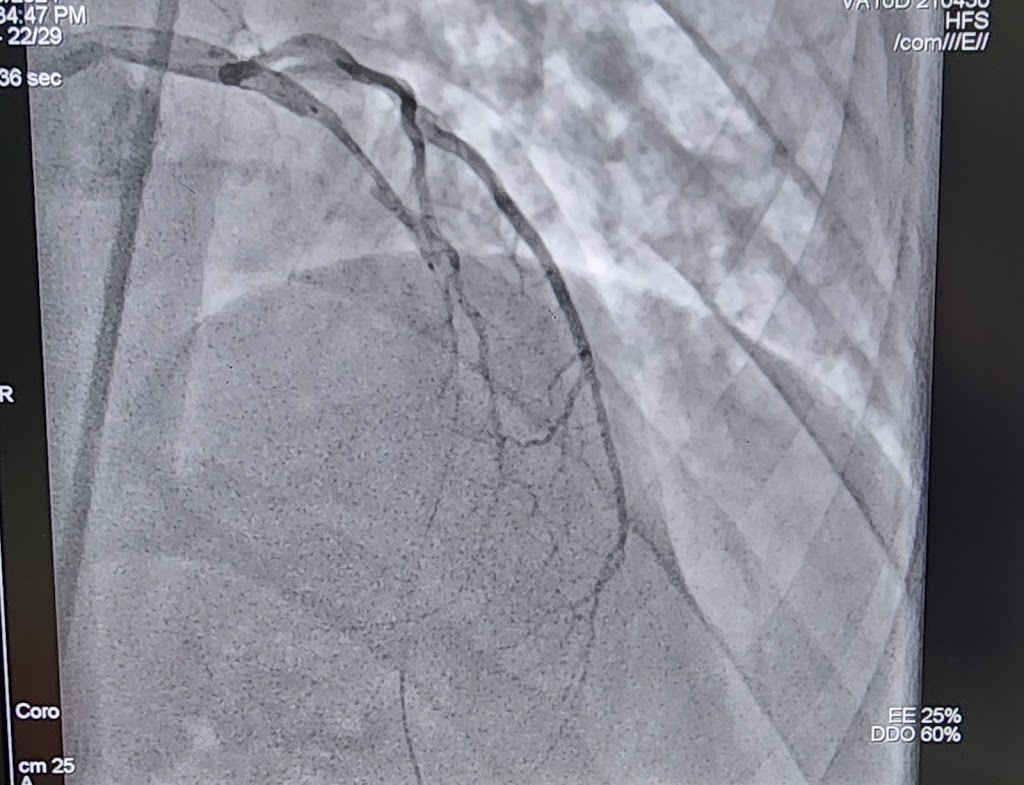

Office Gallery

All

By owner